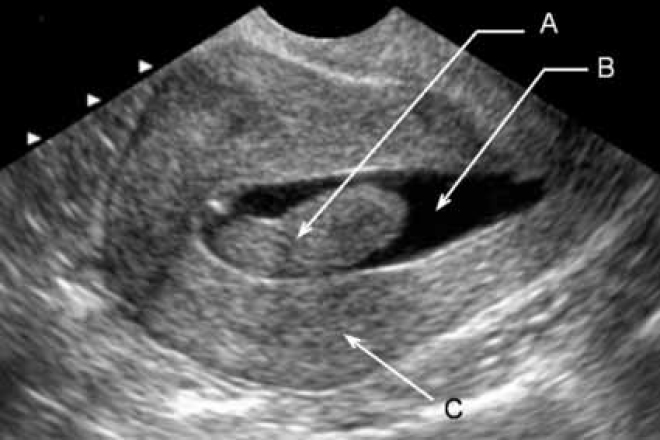

Медицинская диагностика: Гиперплазия эндометрия на УЗИ